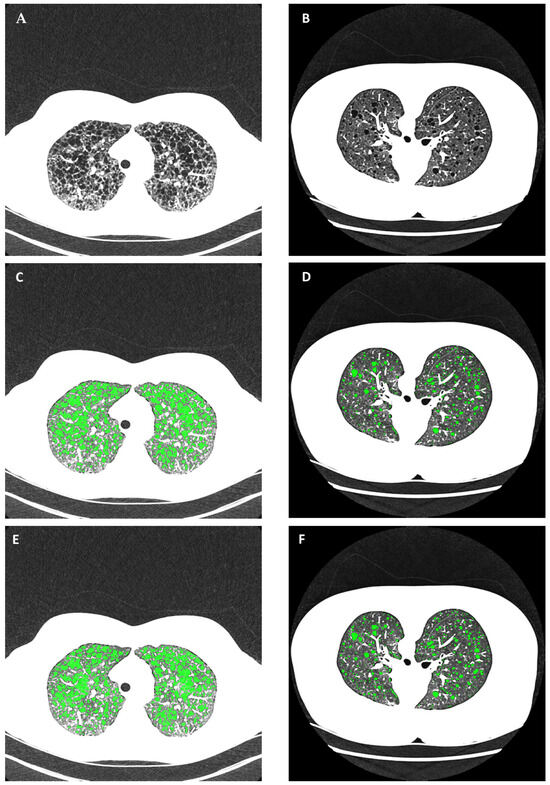

2.4. Automated Cyst Segmentation